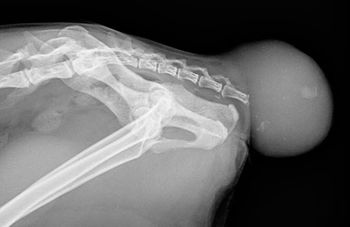

Can you discover the cause?